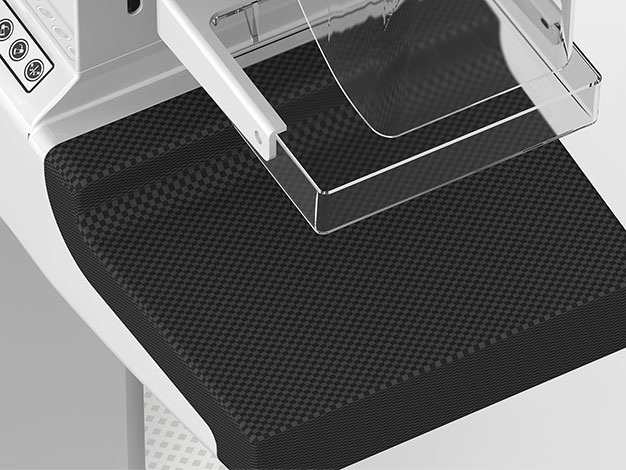

全程温柔舒适

24×30cm大面积成像,

非晶硒/非晶硅平板,随心选择

会思考会记忆,全程温柔呵护

根据不同乳腺密度,选择适宜压力值

自动记忆压迫力度和角度,快速精准

支持手动快速解压